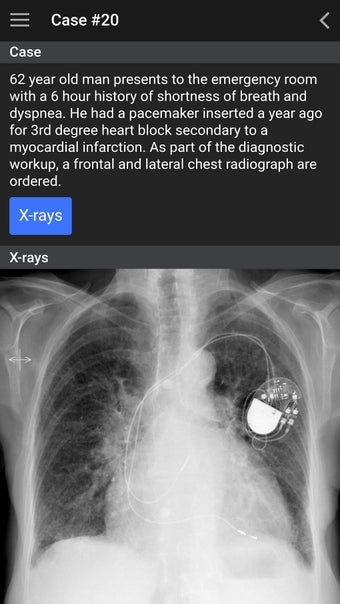

The UBC Radiology app is a free educational tool that aims to help medical trainees increase their confidence in identifying normal anatomic structures and ordering the most appropriate imaging test. The app is based on the radiology undergraduate curriculum at the University of British Columbia (UBC), which is located in Vancouver, British Columbia, Canada.

The UBC Radiology curriculum is designed for medical trainees to learn how to identify normal anatomy and identify common pathology. The curriculum consists of four years of preclinical and clinical studies, where the preclinical years focus on learning to identify anatomy and the clinical years focus on learning to identify and treat patients.

The app will help medical trainees learn how to read an image, identify a structure, and understand the importance of different imaging tests.